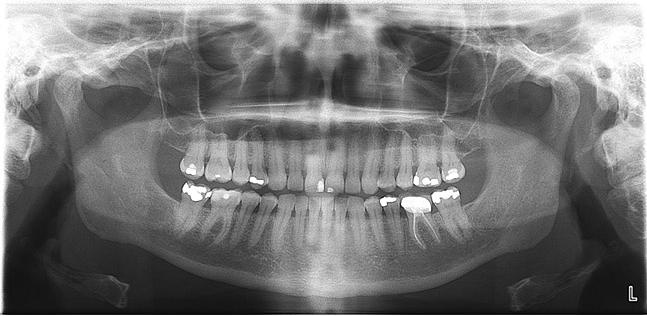

(2.) Panoramic radiographs are options when intraoral radiography is impractical or additional diagnostic information is required.

Figure 2

Panoramic

A digital panoramic radiograph (Figure 2) is indicated for circumstances in which intraoral imaging is not practical, as in patients who cannot open their mouths due to trismus or in those who cannot tolerate having a sensor or film in their mouth due to severe mucositis following radiation therapy for cancer. Advantages of panoramic imaging are that it quickly provides broad coverage of facial bones and teeth, it is convenient for both dental practitioner and patient, and is a helpful visual aid in patient education and case presentation.